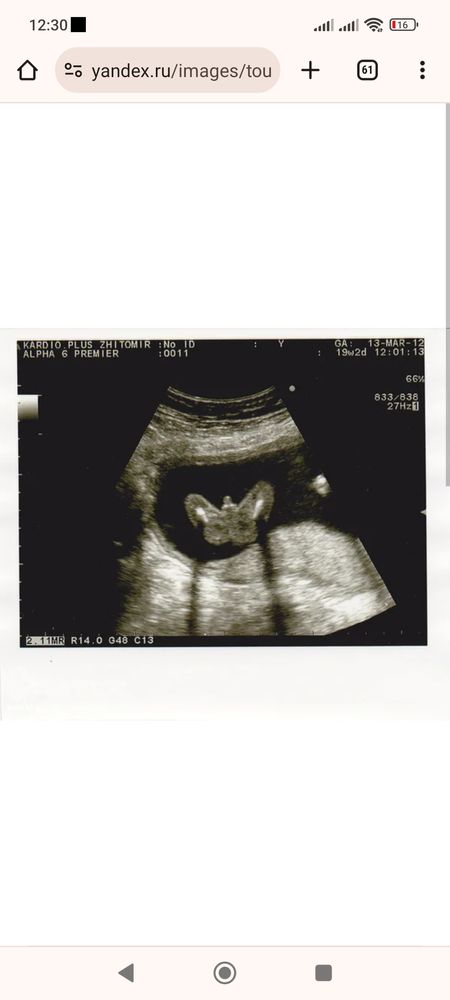

Татьяна, ну я вот к примеру из интернета нашла. У меня два таких УЗИ, с первым ребенком и со вторым. Наверное если вот так показали, то вариантов ошибки просто нет. Понятно что мальчик и в девочку уже не превратиться. А если уши сбоку, ещё и пуповина между ножек, то что можно понять

18.01.2024